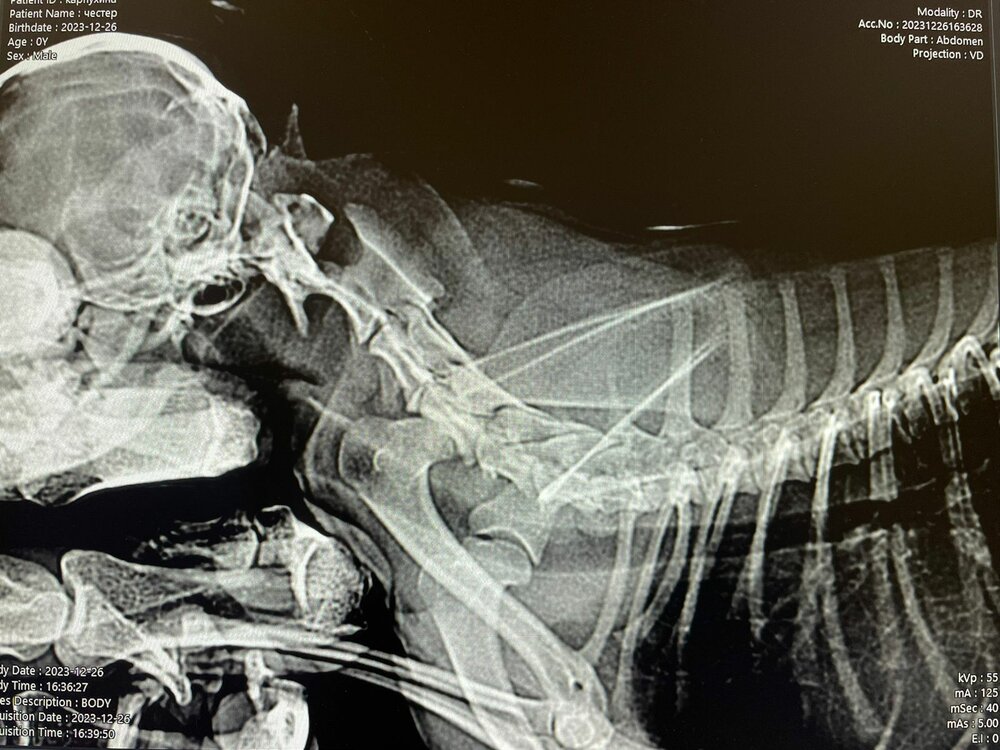

Ребята помогите, у кого был такой диагноз. Собака болеет уже вторую неделю. Врачи ставили разные диагнозы. Лечили нам и уши и живот, пока не доехали в другой город. Диагноз дискоратия грудного отдела. Назначили уколы флексопрофен. Сегодня последний укол, делаем их на ночь. Под утро начинает скулить. Уже и не знаем что делать. Может кто сталкивался, как лечили?

Чихуахуа (IMG-20231226-WA0043.jpg)

138 KB · Просмотры: 151